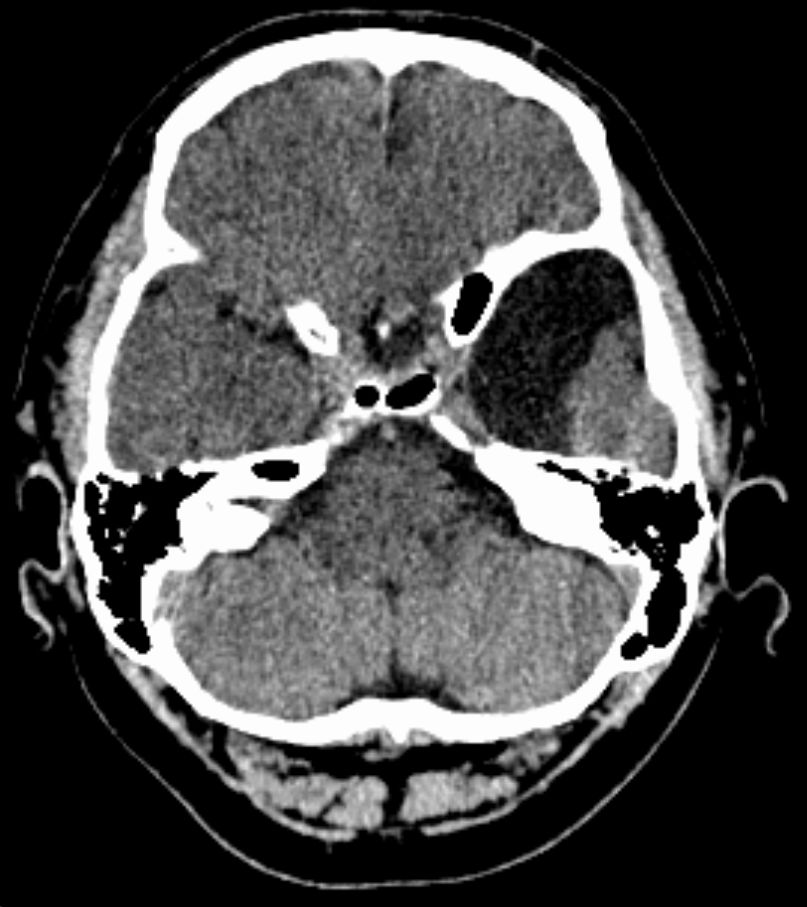

진단은 주로 MRI로 이루어진다. 지주막낭종은 다른 임상적 이유로 MRI를 촬영하는 과정에서 우연히 발견되는 경우가 많다.[9] 실제적으로 증상이 있는 지주막낭종을 진단하려면 증상이 나타나야 하며, 이 질환을 가진 많은 환자는 평생 증상이 나타나지 않는다.

지주막낭종 진단은 주로 MRI로 이루어진다.[9] 지주막낭종은 다른 임상적 이유로 MRI를 촬영하는 과정에서 우연히 발견되는 경우가 많다.[9] 실제적으로 증상이 있는 지주막낭종을 진단하려면 증상이 나타나야 하며, 이 질환을 가진 많은 환자는 평생 증상이 나타나지 않는다.

지주막낭종은 뇌 또는 척추에서 발견될 수 있다. 두개내 지주막낭종은 대개 지주막하 낭포에 인접하여 발생한다.[23] 척추 지주막낭종은 경막외, 경막내 또는 신경주위에 위치할 수 있으며, 신경근병증을 시사하는 징후와 증상을 나타내는 경향이 있다.[23]